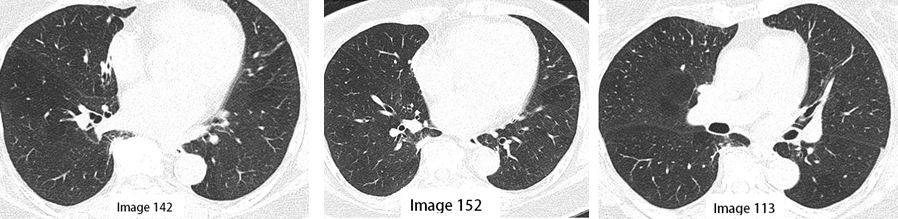

4. Leher/Thoraks: Beberapa nodul paru terlihat bilateral seperti di bawah ini:

• Nodul paru pada segmen medial lobus tengah kanan berukuran 0,4 cm x 0,3 cm (Gambar 142).

• Nodul subpleural kecil pada segmen superior lobus kanan bawah (Gambar 152, 171).

• Nodul terbesar pada fisura horizontal kanan berukuran 0,5 cm x 0,3 cm (Gambar 113).